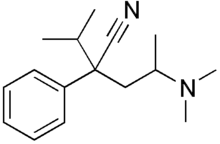

Diphenylpropylamine derivatives

Others